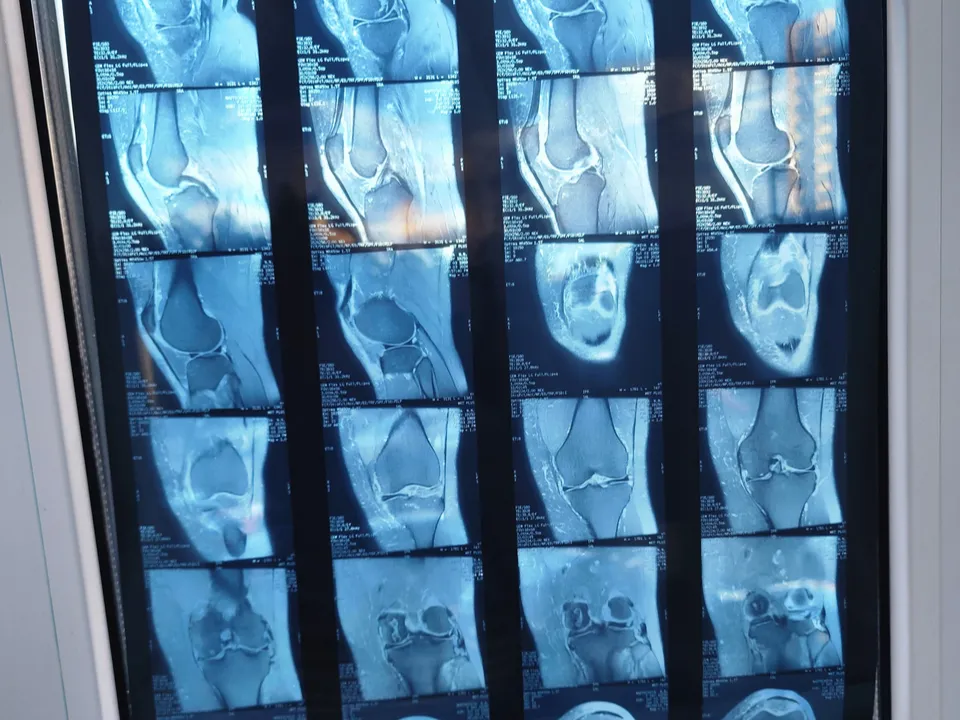

МРТ — это один из самых точных методов диагностики, который помогает выявить заболевания на ранних стадиях. Особенно эффективен он для исследования:

Суставов и костей;